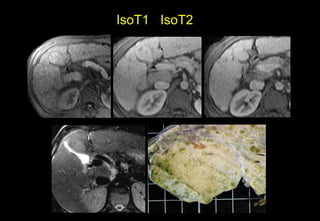

Nốt tân tạo lớn

IsoT1 IsoT2

HypoT1 HypoT2

Ko phải CHC nếu giau sắt

tăngT1 giảm T2Nốt tân tạo lớn